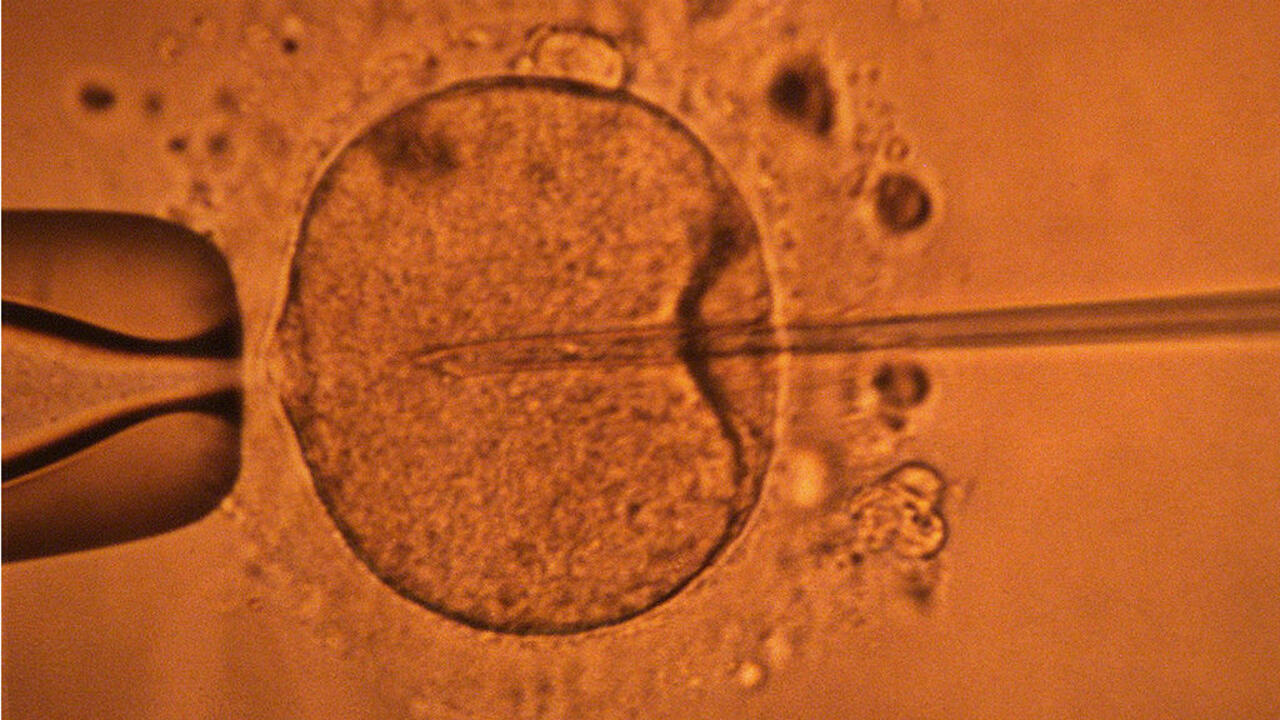

كشفت دراسة جديدة أن عمر الأب يمكن أن يؤثر على صحة الجنين. فكلما تقدم الرجل في السن، زادت فرص ظهور طفرات جينية ضارة في حيواناته المنوية، مما قد يؤثر على فرص الحمل وصحة الطفل....